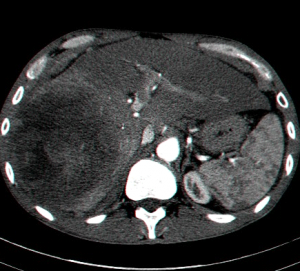

מבחינה פתולוגית שאתות אלה מופיעות לרוב כנגע בודד גדול נודולרי או כנגעים מרובים על פני הכבד כולו. ב- FLC הנגעים בדרך כלל בודדים (75%) ממוקמים באונה שמאלית בעיקר. שאתות ה- HCC הן בעלות מבנה טרבקולרי ועשירות בכלי דם ולעיתים קרובות פולשות לענפים של הווריד הפורטלי ואף לענפים של ורידי הכבד (תמונה 9.10).

- US המראה שאת או מספר שאתות בכבד והוא כלי ראשוני לסקירה ומעקב (תצלום 29.10).

- CT המראה נגעים בכבד. בשאתות קטנות הרגישות של ה- CT ו- US זהה ולכן US משמש לסיקור באוכלוסיות בסיכון גבוה. בעזרת ה- CT ניתן לאתר גם נגעים מחוץ לכבד. ה- CT הספירלי מאפשר לנו לבצע שחזור כלי דם ולהדגים את עושר כלי הדם העוטפים את השאת. ההדגמה ב- CT היא תלת פאזית

- בדרך כלל אין צורך בביופסיה מחטית של הנגע בתנאי שניתן לראות ב- CT מאפיינים קלאסיים ל- HCC. כיוון שה- HCC היא שאת מאוד וסקולרית הרי שהיא "נצבעת" מהר וחזק בשלב ההזרקה ויש שטיפה מהירה בשלב הפורטלי המאוחר (תצלום 30.10-33.10).